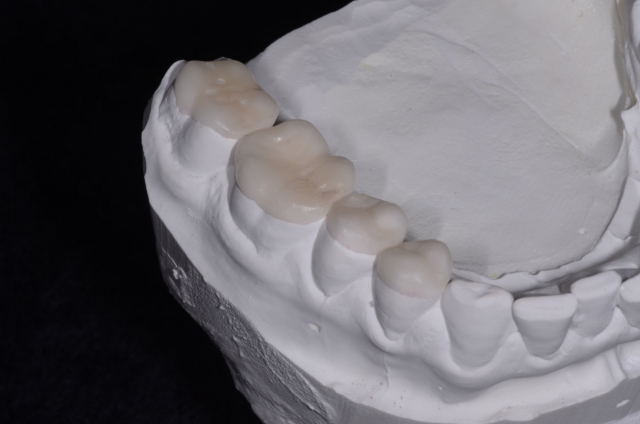

Given I have a CEREC in my office and I wanted to be efficient as possible in treating the case, my decision was to use my CEREC and Vita’s Enamic. I picked Enamic because you can etch it for bonding and I’ve used it many times before so I know it can mill very finely (in fact, less than 0.3 mm thick). Going this route allowed me to premill my no-prep onlays (Fig. 5), and bond them to the teeth (Fig. 6), which saved me a ton of chair time and made things much more efficient.